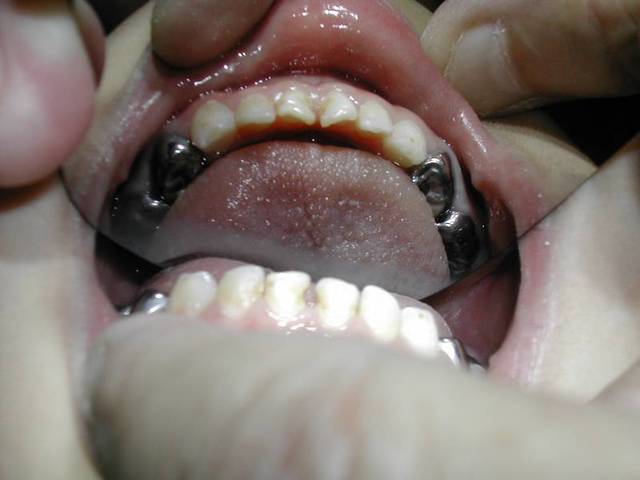

Pour garder l'éspace après éxtraction des C. on fait un arc passif en ligual soudé sur des bagues de 6.

C'est un peu plus difficil en exercice omnipratique, mais il y a des labo Ortho qui font celà très bien.

Il suffit de mettre des élastiques séparateurs entre 6 et 5 de lait, de choisir la bague nue (une boite complète n'est pas chère) de prendre l'empreinte avec les bagues et de l'envoyer au labo.

A vérifier tous les 6 mois, ou tous les ans, et de changer l'arc s'il prend du jeu au niveau du cingulum de incisives.

Si tu as des incisives en linguo-version, tu es en Cl. 2. II. denture mixte. Il faut alors intervenir le plus rapidement possible, car je ne connais pas un seul orthodontiste capable de traiter un Cl. 2 . II. adulte sans contention de 15 ans ou à vie. Il faut donc absolument intervenir le plus tot possible.

P.S.: L'arc soudé aux 6 est lingual. Le stop est le contact avec le cingulum des incisives. Tout est faible à cet age, aussi bien l'ancrage osseux que les forces musculaires.

En cas d'éxtraction de 54/64, je ferais Bagues sur 6 + arc lingual. Mais on peut aussi faire deux mainteneurs d'éspace, dans certains cas.

GC FUJI 1 pour le scellement

pour le suivi,regarde sur la pano le stade d'evolution des premolaires;en general,une visite tous les 3 mois cela suffit